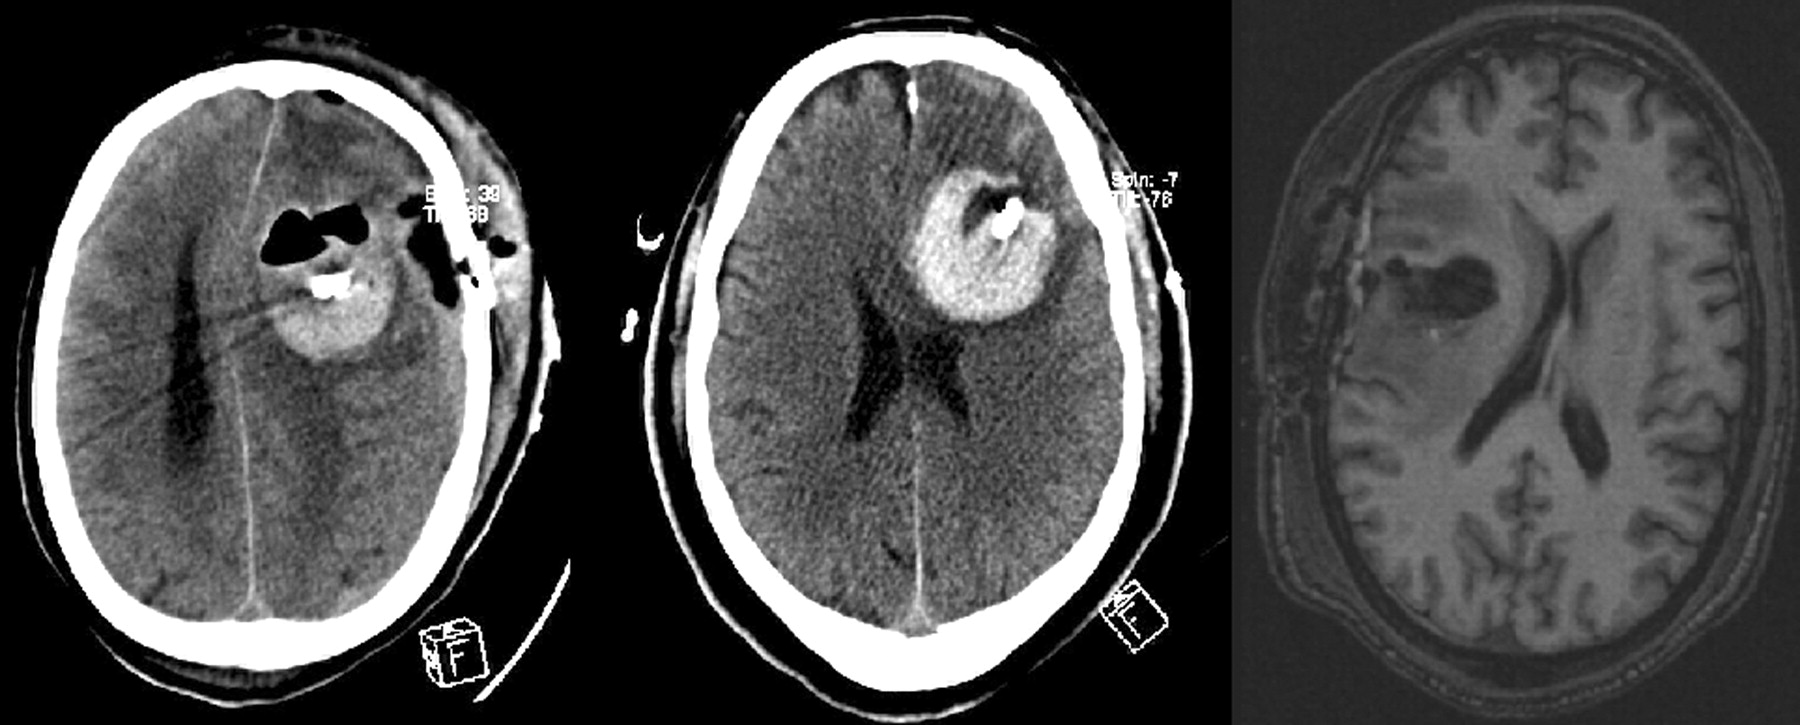

In three patients, the catheters removed in the early postoperative period. One patient had acute postoperative hyponatremia (sodium level=129 mmol/L), followed by brain edema and bleeding requiring an emergency craniotomy for decompression. In another patient, the device was removed because of substantial bleeding around it; this was the result of anticoagulation therapy for bilateral deep venous thrombosis and pulmonary embolus. In the third patient, the catheter was removed because of a change in the therapeutic approach and a lack of catheter conformance. A small amount of blood was present inside the surgical bed, but the distance between the balloon surface and target tissue was more than 1.0 cm; this finding was considered a lack of conformance (Fig 4). None of these three patients had follow-up studies.

Images from the three patients in whom the devices were removed before radioactive unloading. Left, CT scan shows mass effect and bleeding around the device after acute hyponatremia. Center, CT scan shows substantial hemorrhage in the surgical cavity in this patient with coagulopathy. Right, 3D gradient-echo T1-weighted image (3.5/7/1) shows blood products in the surgical cavity and an increased distance between the edges of the balloon and surrounding tissues; this was considered a lack of conformance.